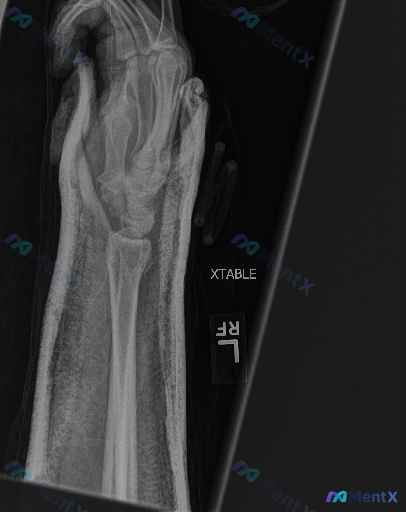

整理到一份右手前臂及手部X光斜位片的影像资料,背景是急性外伤后,主要影像表现如下: 1. 骨骼方面:桡骨远端可见明显骨折线,断端有移位及成角畸形,皮质连续性中断;尺骨茎突位置也见骨折断端,有移位;掌骨及近节指骨可见范围内未见明确骨折线。 2. 关节方面:腕关节解剖结构因骨折发生改变,关节面移位、对合...

整理到一张右侧手腕X光正位片的影像资料,先把关键表现列出来,大家看看这种情况第一反应会往哪些方向考虑? 关键影像表现 1. 骨骼完整性: - 桡骨远端关节面可见横行透亮骨折线,累及关节面,骨皮质不连续,骨折端无明显移位; - 尺骨茎突可见撕脱性骨折征象,骨折块位置清晰; - 舟骨、月骨、三角骨等腕骨...